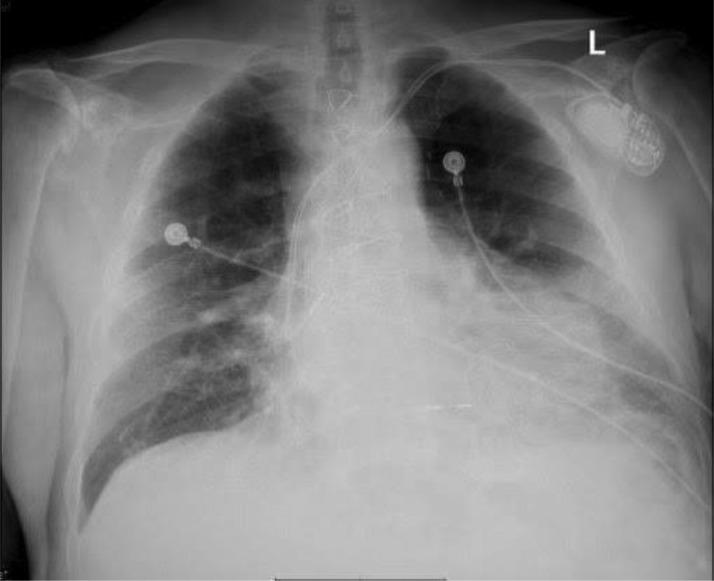

Hemarthrosis secondary to heparin use is a scarce event, especially in patients with no underlying thrombophilia or platelet disorders. Although previously associated with thrombophilia, platelet disorders, or secondary to fibrinolytic therapy, to date, there are very few reported cases in contemporary literature for heparin-induced hemarthrosis. In this article, we report a case of left shoulder joint inferior subluxation secondary to heparin-induced hemarthrosis in an 81-year-old male with an extensive cardiac history and multiple comorbidities. This case report depicts a rare event and discusses its clinical implications aiding healthcare professionals in an early diagnosis and timely management.

肝素使用继发的关节积血是一种罕见事件,尤其在没有潜在血栓形成倾向或血小板疾病的患者中。尽管以前与血栓形成倾向、血小板疾病相关,或继发于纤维蛋白溶解疗法,但迄今为止,当代文献中关于肝素诱导的关节积血的报道病例非常少。在本文中,我们报告了一例81岁男性因肝素诱导的关节积血继发左肩关节半脱位的病例,该患者有广泛的心脏病史和多种合并症。本病例报告描述了一个罕见事件,并讨论了其临床意义,以帮助医护人员进行早期诊断和及时处理。